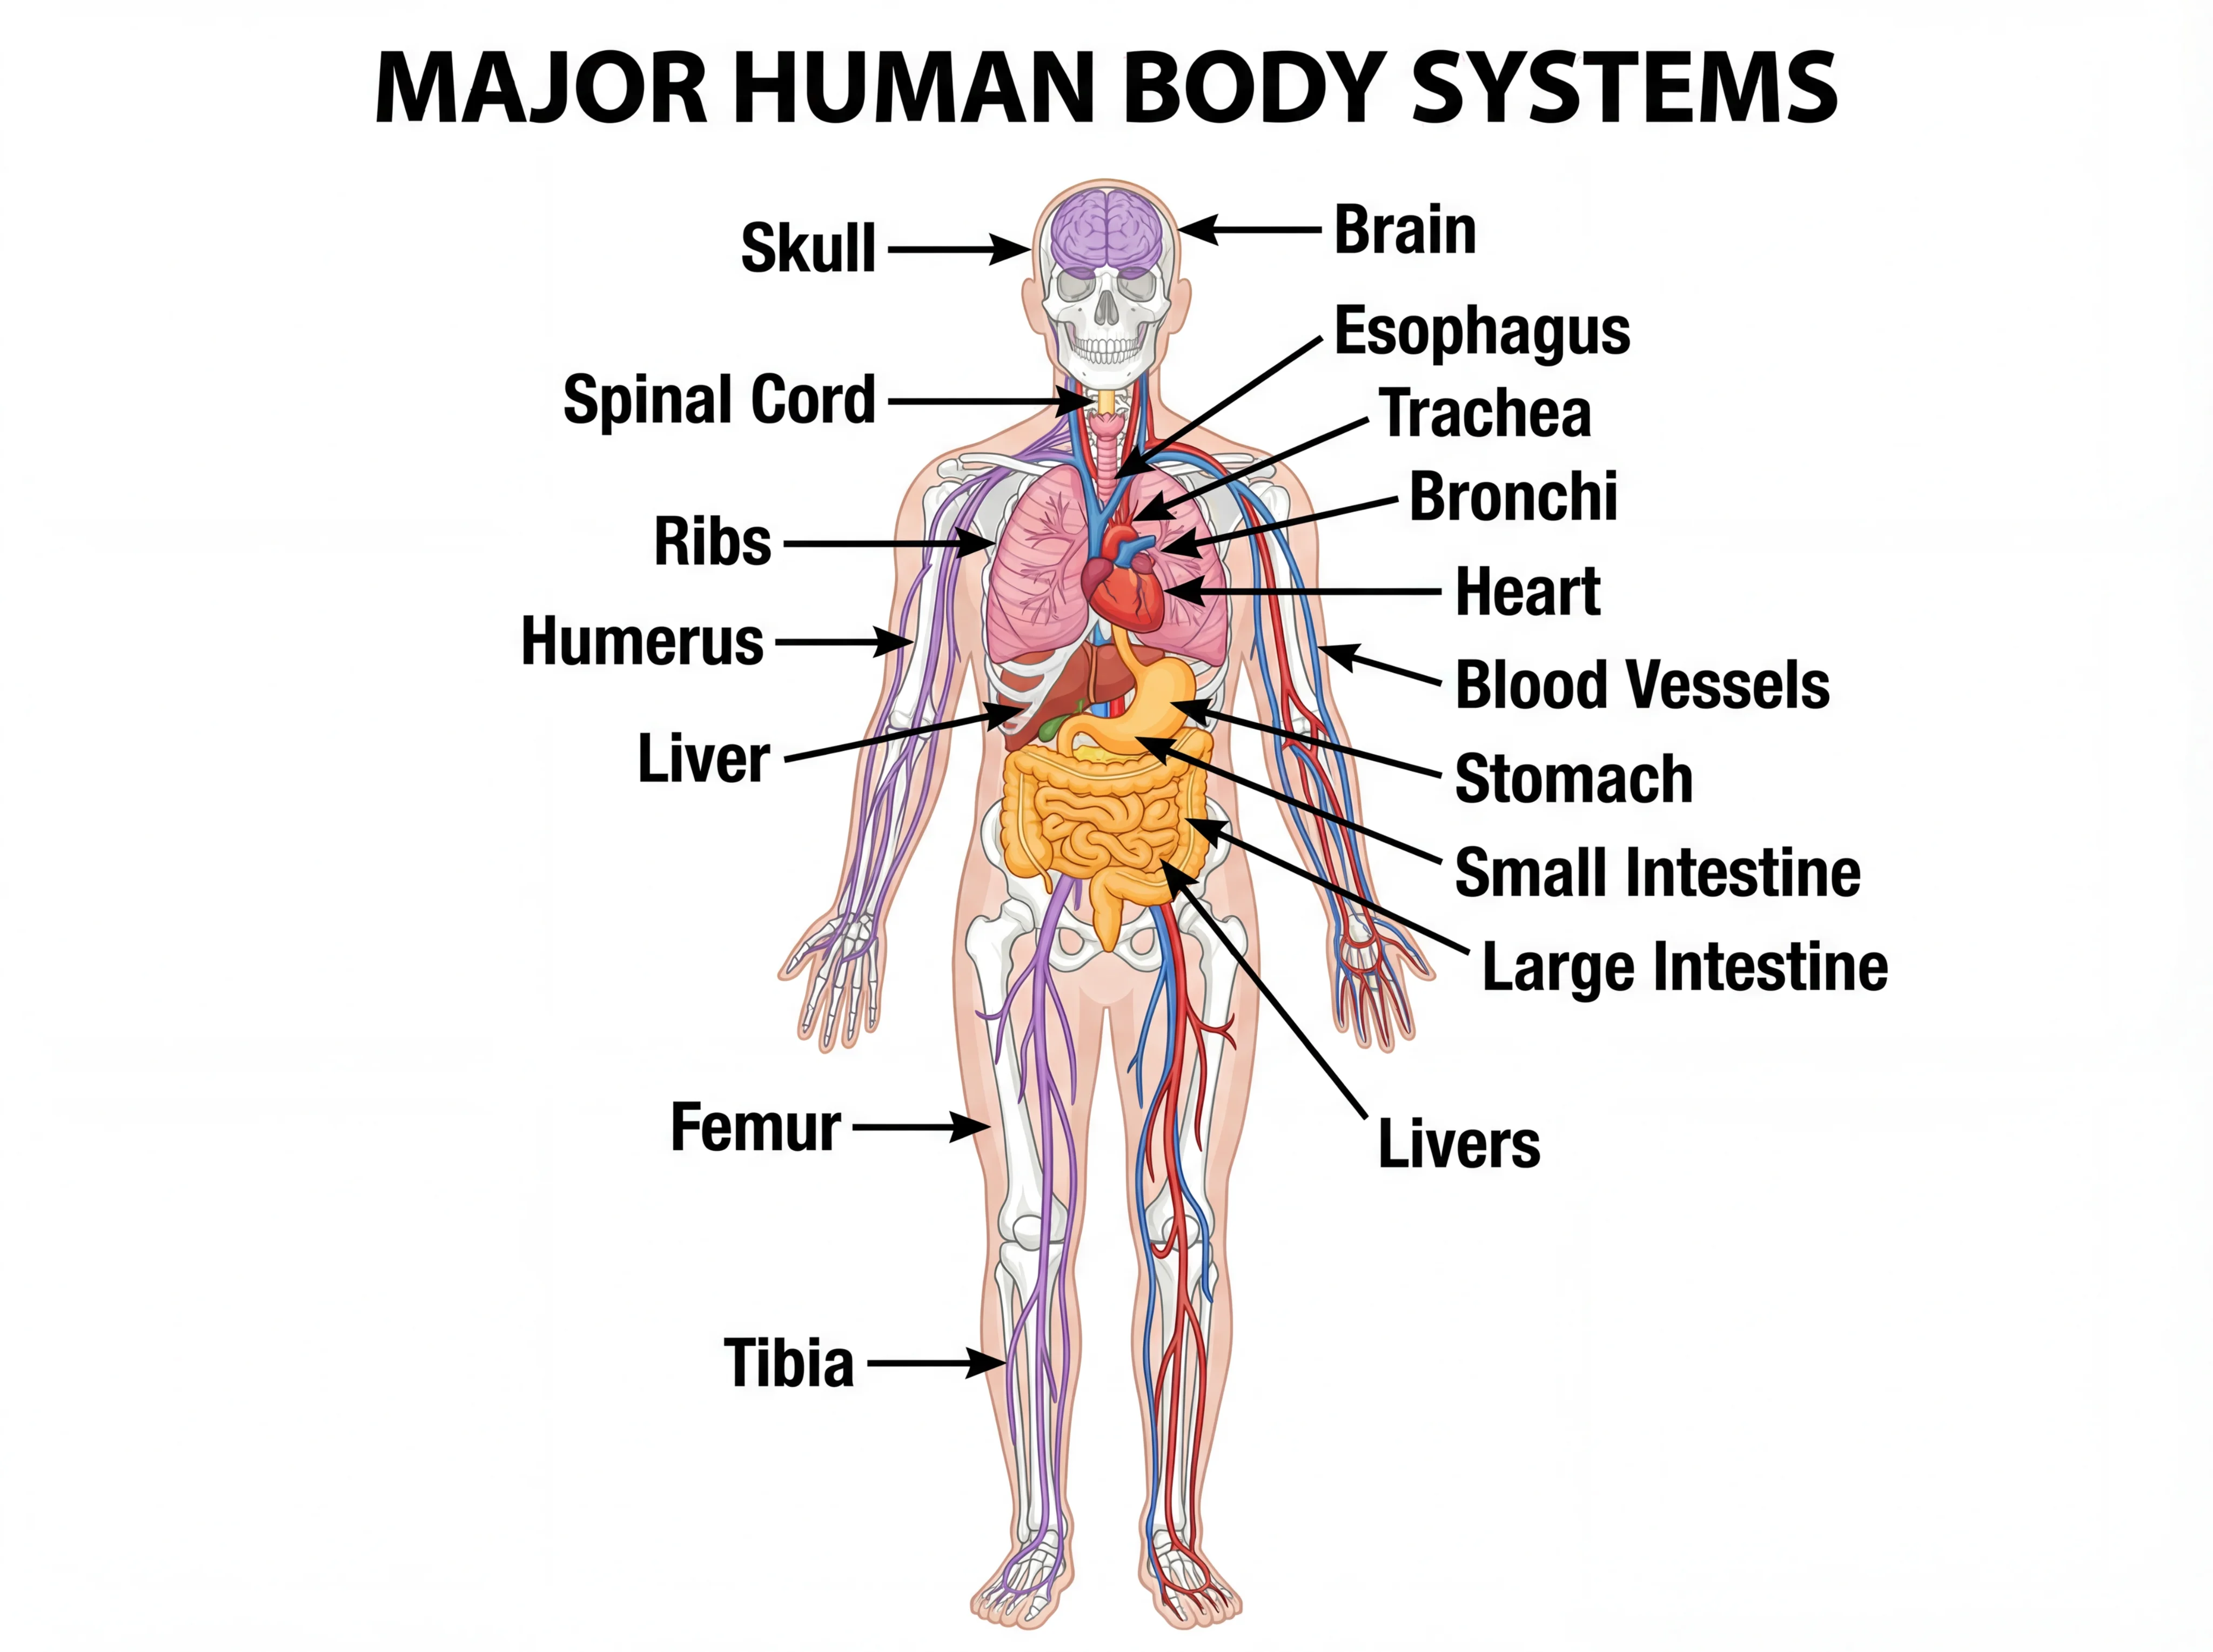

Anatomical Drawing Generator Human Anatomy Visualized

Generate professional anatomical drawings and anatomy illustrations with AI. Create skeletal, muscular, organ, and body system diagrams for education and medical training.

Professional anatomy illustrations for education and medical training

What is Anatomical Drawing Generator?

Anatomical Drawing Generator is an AI-powered tool that creates professional anatomy illustrations for education and medical training. Whether you need skeletal system diagrams, muscular anatomy, joint structures, or detailed body part illustrations, our AI generates accurate, educational-quality anatomical drawings in seconds. Perfect for anatomy teachers, medical students, physical therapists, and healthcare educators who need clear anatomical visuals.

Anatomical drawings are essential for anatomy education and healthcare training. Use them for anatomy courses, medical school lectures, physical therapy education, nursing programs, athletic training, and patient education. Our AI understands anatomical terminology and conventions, producing visuals that accurately represent human body structures for effective learning.

BiologyHuman Body Systems Diagram Generator

Create detailed human body systems diagrams for anatomy education.